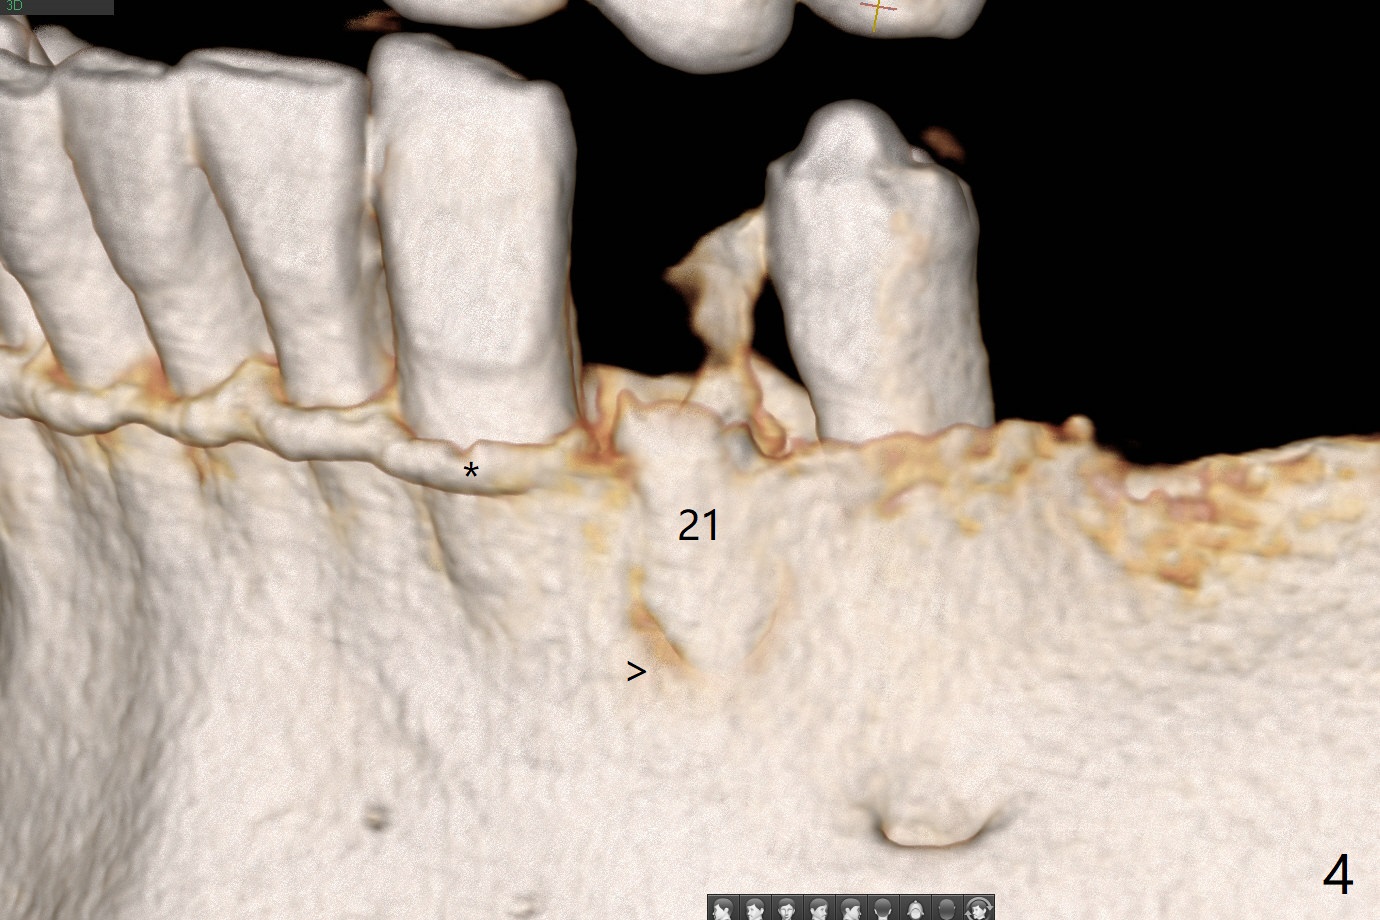

A 52-year-old man chooses to take care of the teeth #21 and 29 first due to finance (Fig.1). The implant diameter should not be too large because of the moderate mesiodistal space (Fig.2,3). Since the buccal plate of #21 is indistinct (socket shield will be done), the implant should be a little more lingually placed than the design in Fig.3, although the implant placement level seems to be acceptable. Socket shield seems to be necessary.